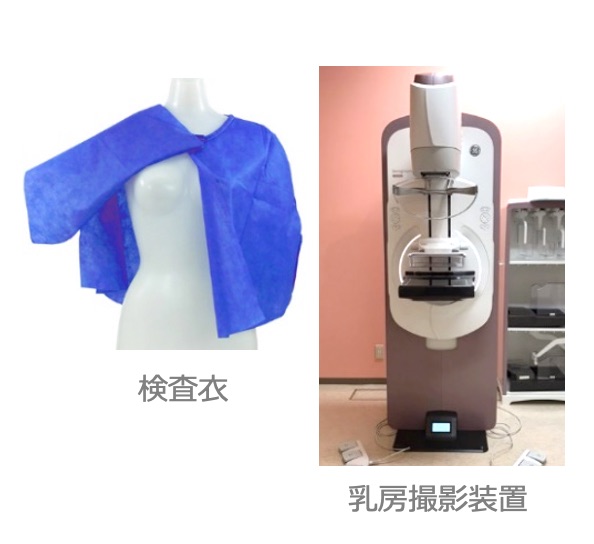

マンモグラフィ: Mammography(乳房撮影)

当院はマンモグラフィ検診精度管理中央委員会による施設認定(マンモグラフィ検診施設画像認定)を受けており、精度の高い撮影や機器管理に日々努めています。また検診マンモグラフィ撮影技術認定の診療放射線技師を中心とした女性技師が検査を担当しています。

- 軟X線(通常のX線撮影より弱いX線)を使⽤し乳房の様⼦を撮影します。

- 検査室内で専⽤検査⾐に着替えて頂きます。

- 画質向上、被ばく低減のために乳房を圧迫します。

- 圧迫時間は1回につき約20秒です。

- 撮影回数は個⼈差があります。

(必要により多⽅向撮影や拡⼤撮影を⾏います)

●次の⽅は撮影時お申し出下さい。

- 妊娠中の⽅

- 授乳中の⽅

- ペースメーカーを装着している⽅

- 豊胸⼿術をしたことがある⽅

- その他、撮影に不安のある⽅

●マンモグラフィのよくある質問